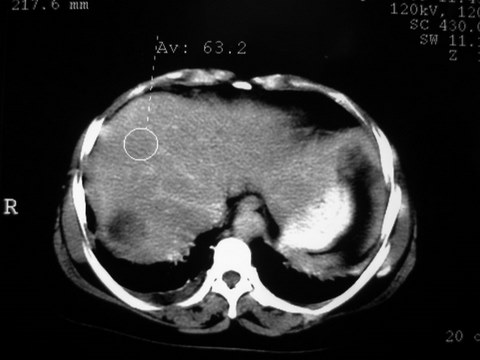

患者 女 51岁 两天前感觉上腹疼,无明显诱因,b超示肝右叶囊实性占位,边缘清楚,其内回声不均匀,ct增强如图,大家看看是什么 ,病人一年前及两月前b超检查只是提示胆囊炎

外院术后,证实肝癌合并出血

增强扫描好像都没有强化的,不管灶周还是灶中心,支持考虑包虫病,别不除外肝囊内内出血,那些一块一块的为血凝块

出病理 中分化肝细胞癌合并出血